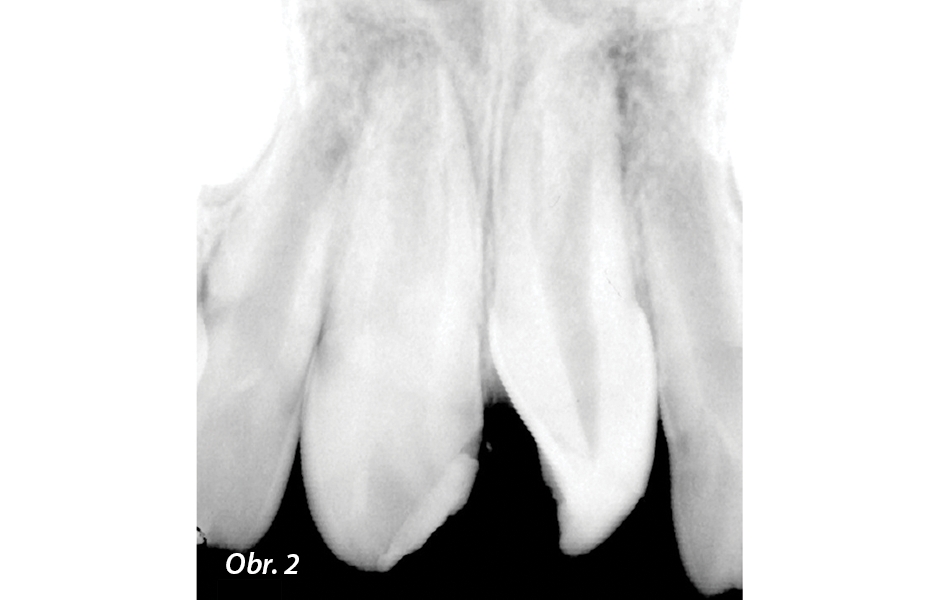

Jedenáctiletá pacientka byla referována pro posouzení a možné ošetření traumatické intruze. Pacientka i matka sdělily, že před dvěma týdny, po pádu z kola, došlo k úrazu stálých horních středních řezáků (zuby 11, 21), následně ošetřených na pohotovosti. Pokusy o získání klinických údajů a popisu provedeného ošetření proběhly neúspěšně. Klinické vyšetření odhalilo rozsáhlou frakturu korunky zasahující sklovinu i dentin, s přidruženou intruzí a rotací (obr. 1), způsobenou nárazem v ose zubu, a normálními měkkými tkáněmi. Na škále od 0 do 3 byl stupeň viklavosti zubů hodnocen stupněm 0 až 1. V klinických testech byly oba řezáky citlivé na poklep a nereagovaly na test vitality chladem (Hygenic Endo-Ice; Coltene). Rentgenové periapikální vyšetření ukázalo otevřené apexy a absenci radiolucentní léze v apikální oblasti poškozených zubů, atypické umístění obou zubů, výraznou traumatickou intruzi a rotaci (obr. 2). Diagnóza byla nekróza dřeně a asymptomatická apikální periodontitis.

RTG snímek zachycující horní řezáky s traumatickou intruzí (zub 11) a intruzí a rotací (zub 21). Vidět je i neúplné vytvoření kořenů a otevřené apexy.